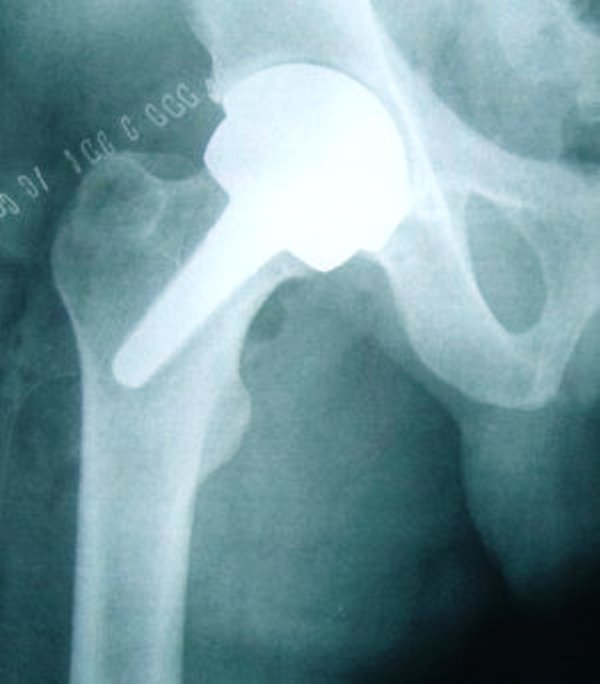

Il “successo” della chirurgia dell’anca dipende soprattutto dall’avvento di nuovi materiali, caratterizzati da un’usura estremamente inferiore rispetto al passato e con prestazioni ottimali a lungo nel tempo. «Le protesi del passato avevano una vita media di circa 15 anni per i pazienti anziani, 8 per i più giovani e attivi. – spiega Marco d’Imporzano, presidente del Congresso Nazionale SIOT e direttore del Dipartimento di Ortotraumatologia dell’Istituto Ortopedico Gaetano Pini di Milano – I materiali che abbiamo a disposizione oggi possono in teoria arrivare facilmente a 30 anni o perfino oltre. Non esiste ancora la protesi ‘eternà, ma con i nuovi materiali è possibile allungarne la vita in modo impensabile fino a qualche anno fa».

Le nuove protesi stanno segnando anche una nuova tendenza: garantendo una durata maggiore vengono infatti impiegate sempre più spesso in soggetti giovani. «Non aspettiamo più che la persona sia anziana per intervenire, se la qualità di vita è già notevolmente compromessa – spiega d’Imporzano – e ormai non è raro intervenire su 30-40enni e ogni anno sono 20.000 le protesi che vengono impiantate in under 65. In questi casi si scelgono soprattutto le protesi in ceramica: materiali che hanno una bassissima usura e ridotto rischio di rottura». –